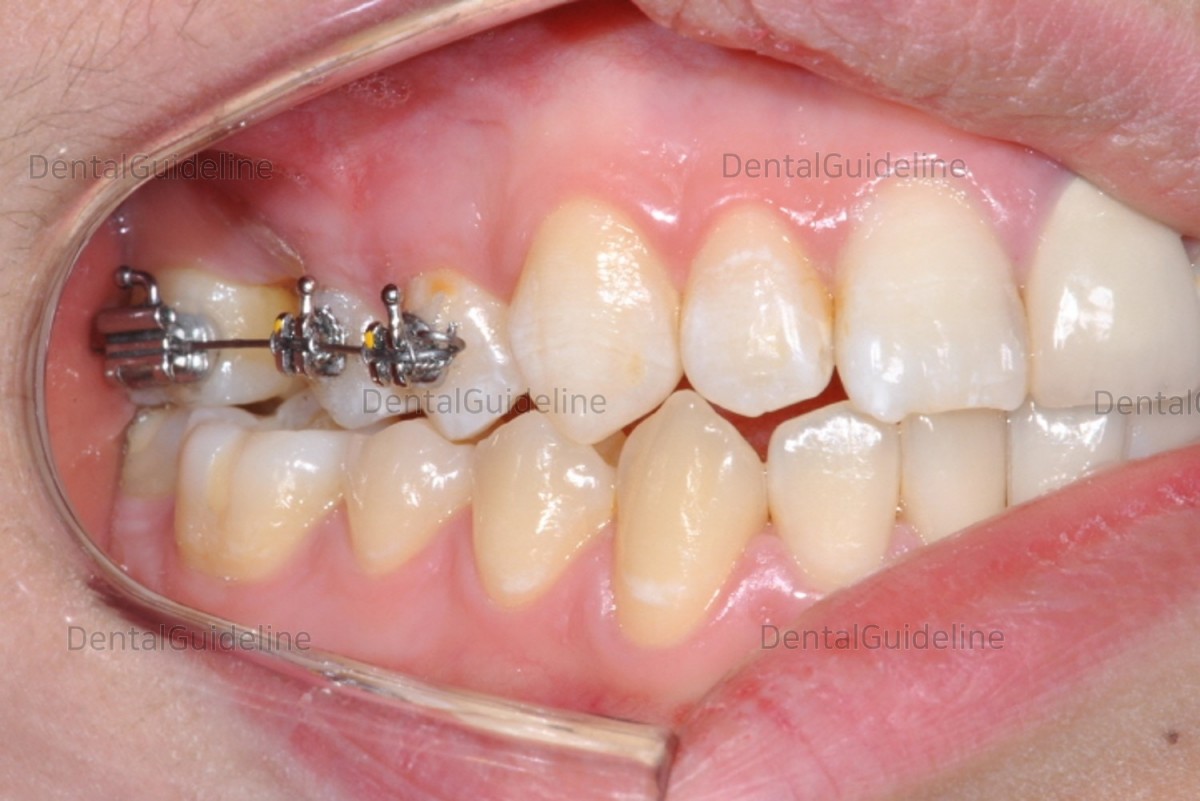

14. The bracket was bonded and the segment wire was ligatured.

15. 50 days after orthodontic treatment. (coated Ni-Ti open coil spring)

![]()

16. 85 days after orthodontic treatment